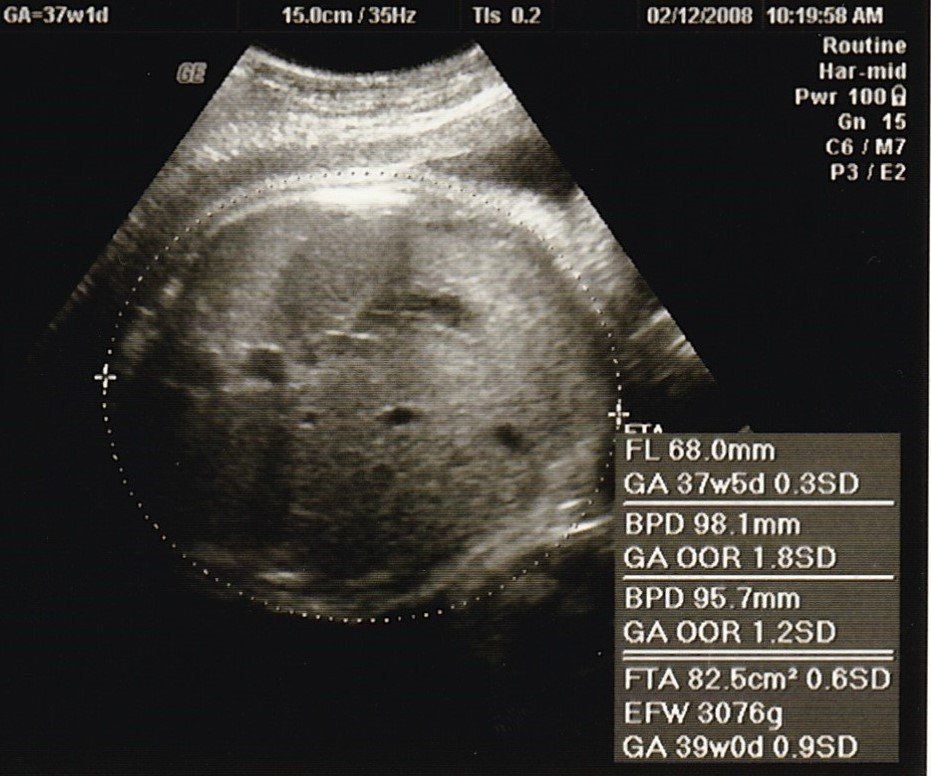

妊娠37週目のエコー写真

推定体重3000gにまで増えていてビックリ。私自身が2600gで生まれており、「お産は母親に似る」と聞いていたので、勝手に少し小さめで生まれてくると思っていました。「4000g超えになるかも」と不安を覚えました。私は既に10kg近く増加になっていたので、この時期から意識的に散歩と、食べすぎに気をつけ、臨月は赤ちゃんの増加分(約1kg)にとどめ、最終的に10.5kg増で抑えました。